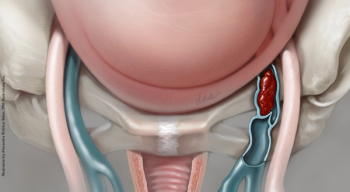

Chronic pain appears to play a major role in the relationship between endometriosis and depression, according to a recent meta-analysis.

New research compared the effectiveness of MRI and TVS for detecting rectosigmoid endometriosis.